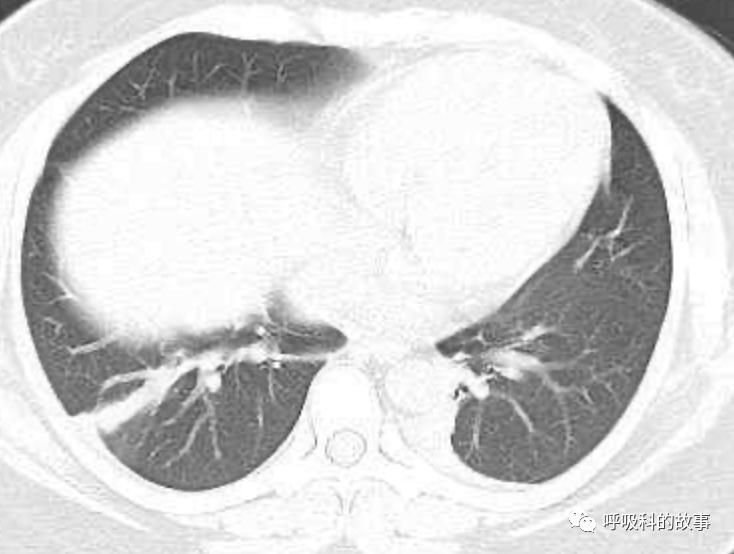

患者发热后行胸部CT检查(6月21日,住院第13天),可见两下肺有条片影,当时考虑是肺炎引起的发热。

可是在6月26日(往院第18天)仍持续发热的情况下复查肺部CT,肺部病灶已明显吸收了。那么患者发热的原因到底是什么呢?为什么患者高热的情况下血白细胞不升反降,C反应蛋白也没有明显增高?这个时候消化科医生也迷茫了,这可怎么办?于是请感染科和呼吸科医生一起会诊,共商计策。